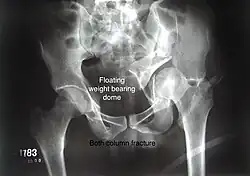

Both column fracture showing floating weight bearing dome -

Combined both column fractures | These are the most complex injuries. Here the weight bearing roof or dome of the acetabulum is a floating piece. This adds to complexity of management.

All three x-ray views plus CT scan is a must for diagnosis and management of this complex injury.